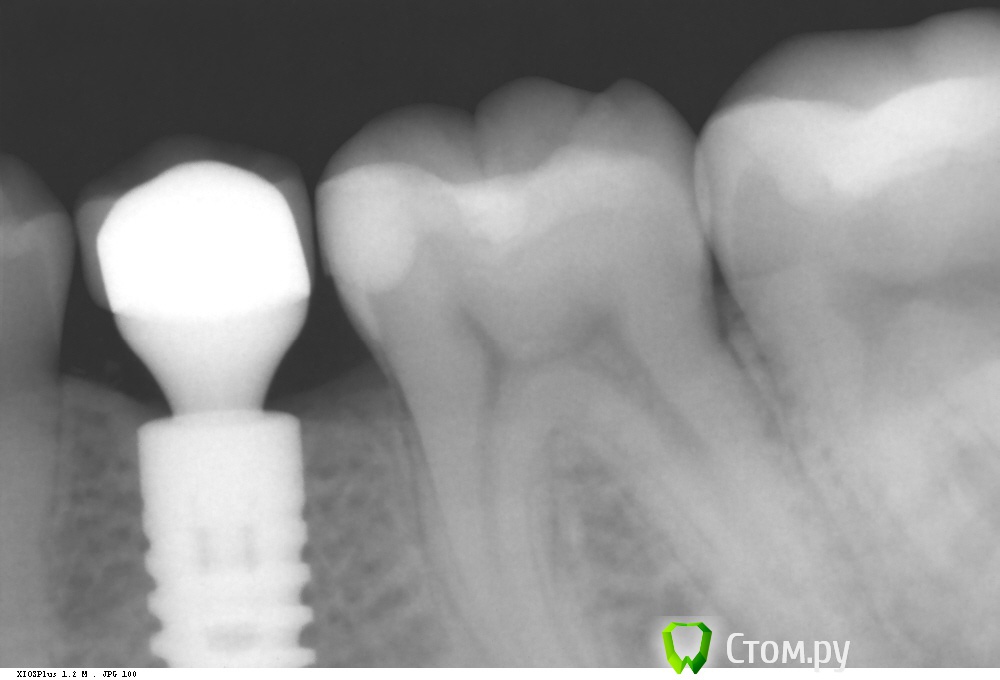

Dr.Sham Опубликовано 8 октября, 2014 Поделиться Опубликовано 8 октября, 2014 Удаление в другой клинике. КТ. Установка имплантата. кость была мягкая, но была со всех сторон по 2 мм минимум. Рентген оч жесткий. Через 2 месяца раскрытие имплантата, имплантат был окружен костью, как обычно, пришлось его раскапывать. ФДМ. Заживление без особенностей. Сегодня была фиксация коронки, сделал рентген для проверки фита. И...потерял дар речи. Десны маловато, но вокруг все кератинизировано. ФДМ узкий был. C чем может быть связана резорбция? Ссылка на комментарий

Дмитрий Никитюк Опубликовано 9 октября, 2014 Поделиться Опубликовано 9 октября, 2014 Вопрос: БШ на имплантате от чего до чего высчитывается? от края десны до шейки имплантата?Нет конечно. На разборных имплантатах от места соединения имплантата с абатментом (формирователем). Посмотрел Ваш снимок ещё раз, Вы таки должны были поставить имплантат глубже, у Вас всего 3,5 ММ ОТ ЦЭС: http://s019.radikal.ru/i630/1410/35/3fd6906e7fae.png + поддесневой профиль неоптимальный + не дождались формирования замыкающей пластинки 1 Ссылка на комментарий

Дмитрий Никитюк Опубликовано 9 октября, 2014 Поделиться Опубликовано 9 октября, 2014 Спасибо за содержательные ответы. Поддесневой профиль обусловлен стандартным абатментом. Если бы взяли следующий абатмент, то уступ торчал бы из десны. С этой проблемой часто сталкиваюсь: абатменты идут 0,75 1,5 и сразу 3 мм. Часто хочется 2 мм. Может я что-то не так делаю...зачем тогда производитель их создал. по хирургии рекомендации я учел, но в рекомендациях производителя заглубление не на 2 мм. опять же, я не спорю, просто констатирую. по БШ и ремоделировке в толк не возьму. Если он всегда и везде есть, можете на пальцах объяснить, что более выигрышно на анкилосе? что мы все это в глубине кости скрываем? ПС как определить, дождался я или нет формирования замыкательной пластинки? я поднимал эту тему как-то на форуме, счас найду ссылку, вразумительного ничего не получил. Если не сложно, прокомментируйте и ее. Второй пациент задинамил, сижу веб-серфингом занимаюсь Вот тема: http://forum.stom.ru/topic/26049-rezorbtciia-posle-udaleniia/?do=findComment&comment=435670 Нам всем не хватает академического образования… Озвученные Вами вопросы являются базовыми. Странно, что человек, который имеет допуск к имплантологии не знает на них ответы. Но это скорее минус ситеме образования… Мне тяжело ответить на столь объёмный вопрос в формате форума. Для меня многие вещи являются очевидными, и не требующими никаких объяснений и доказательств. По поводу замыкающей пластинки, то на этот вопрос я уже ответил вчера в соседней ветке. На КТ она чётко видна, в том случае через 4 месяца после удаления. Её видно и на прицельном снимке. Но это не значит, что имплантат нельзя устанавливать раньше. Разница лишь в прогнозе вертикального положения костной ткани после полного заживления. Поддесневой профиль не может быть обусловлен абатментом, если работа бюджетная, делайте на стандартном абатменте с латеральной винтовой фиксацией. Оптимальная высота абатмента на Анкилозе 3 мм, запомните как аксиому, без вопросов. Меньше - плохо. Рекомендации производителя идут в разрез с рекомендацией практикующих врачей, поэтому рекомендую прислушаться к мнению Марко Дегиди, например, который их установил десятки тысяч. Я пришёл к этому через 2 года работы с системой после анализа своих работ, а мог начать так делать раньше, если бы кто подсказал, так как я Вам сейчас. Запомните, что любой имплантат с переключением платформ нужно ставить глубже, так как для формирования оптимального профиля понадобится больше места по вертикали. Очень надеюсь, что Вы знаете как работает переключение платформ. Но немного напомню. Переключение платфор сещает зону инфильтрата коронарно, таким образом вертикальная резорбция значительно уменьшается или вообще отсутствует. А конусное соединение на Анкилозе очень герметично, поэтому имплантат работает практически как монолитный, колличество м/о в соединении минимально, при этом там живут только мелкие микроорганизмы, нет коллоний, а соответственно имунный ответ минимальный и диаметр инфильтрата меньше, поэтому резорбция или отсутствует (так уверяет производитель), или она минимальная щелевидная. Я ни в коем случае не претендую на роль ментора, Вы спросили, я ответил. Всё что касается переключения платформ и конусного соединения справедливо и для других систем подобной конструкции, а не только Анкилоза. 7 Ссылка на комментарий